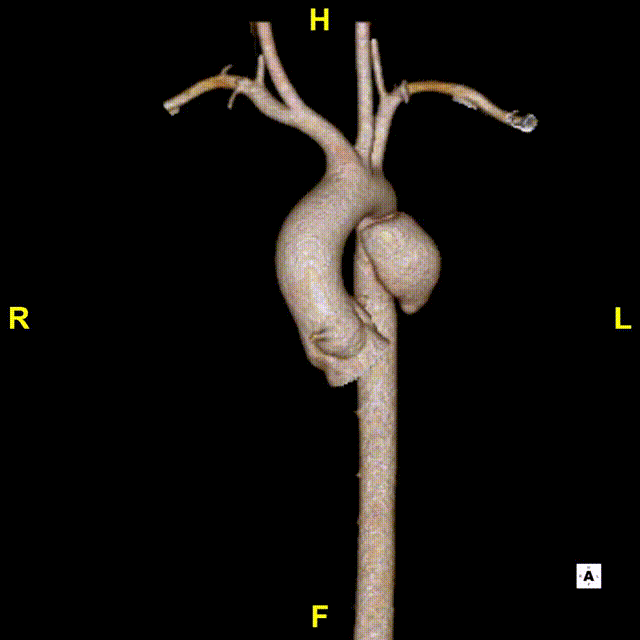

患者女性,15岁,因意外高空坠落收治入院。患者入院后行CTA检查,可见主动脉峡部局限夹层,小弯侧距离左锁骨动脉后缘锚定距离7.9mm,患者年纪小,主动脉直径较细。

术前3D重建

锚定区距离

血管直径